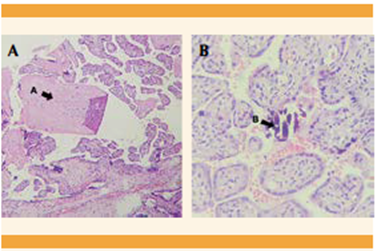

Con la intención de mejorar la oxigenación y la condición respiratoria y evitar el empeoramiento del estado clínico se decidió finalizar el embarazo mediante cesárea tipo Kerr, que trascurrió sin complicaciones y la obtención de una recién nacida, de 735 gramos. De inmediato se trasladó a la unidad de cuidados intensivos neonatales; falleció a los 16 días posteriores debido a un choque cardiogénico, peritonitis generalizada, perforación intestinal, enterocolitis necrotizante y sepsis temprana. La histopatología placentaria reportó: vellosidades coriónicas del segundo trimestre, con depósito fibrinoide perivelloso, con calcificación distrófica focal y áreas de infarto. Figura 6

Figura 6 Microfotografía de las vellosidades coriales del segundo trimestre. (A) Fibrinoide perivelloso. (B) Calcificación distrófica focal.